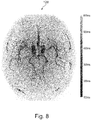

• Fig. 8 shows an example of a composite angiographic image 128 that was constructed using the static angiographic image 114 and the time series of angiographic images 116' from Figs. 5 and 6 .

• the composite angiographic image is a mapped TOF angiographic image with the temporal information from ASL presented as time of arrival map. Since ASL images only present arterial vessels, the presented image analysis can avoid visualization of venous vessels which may appear in QF images due to technical issues such as insufficient saturation as was indicated in Fig. 7 . It is noted that the artifacts illustrated in Fig. 7 are not present in Fig. 8.

• FIG. 8 shows a mapped TOF image with the temporal information from ASL presented as a time-of-arrival map. Since ASL images only present arterial vessels, the presented image analysis can avoid the visualization of venous vessels which may appear in TOF images due to technical issues (insufficient saturation). This can be indicated as in Fig. 7 .